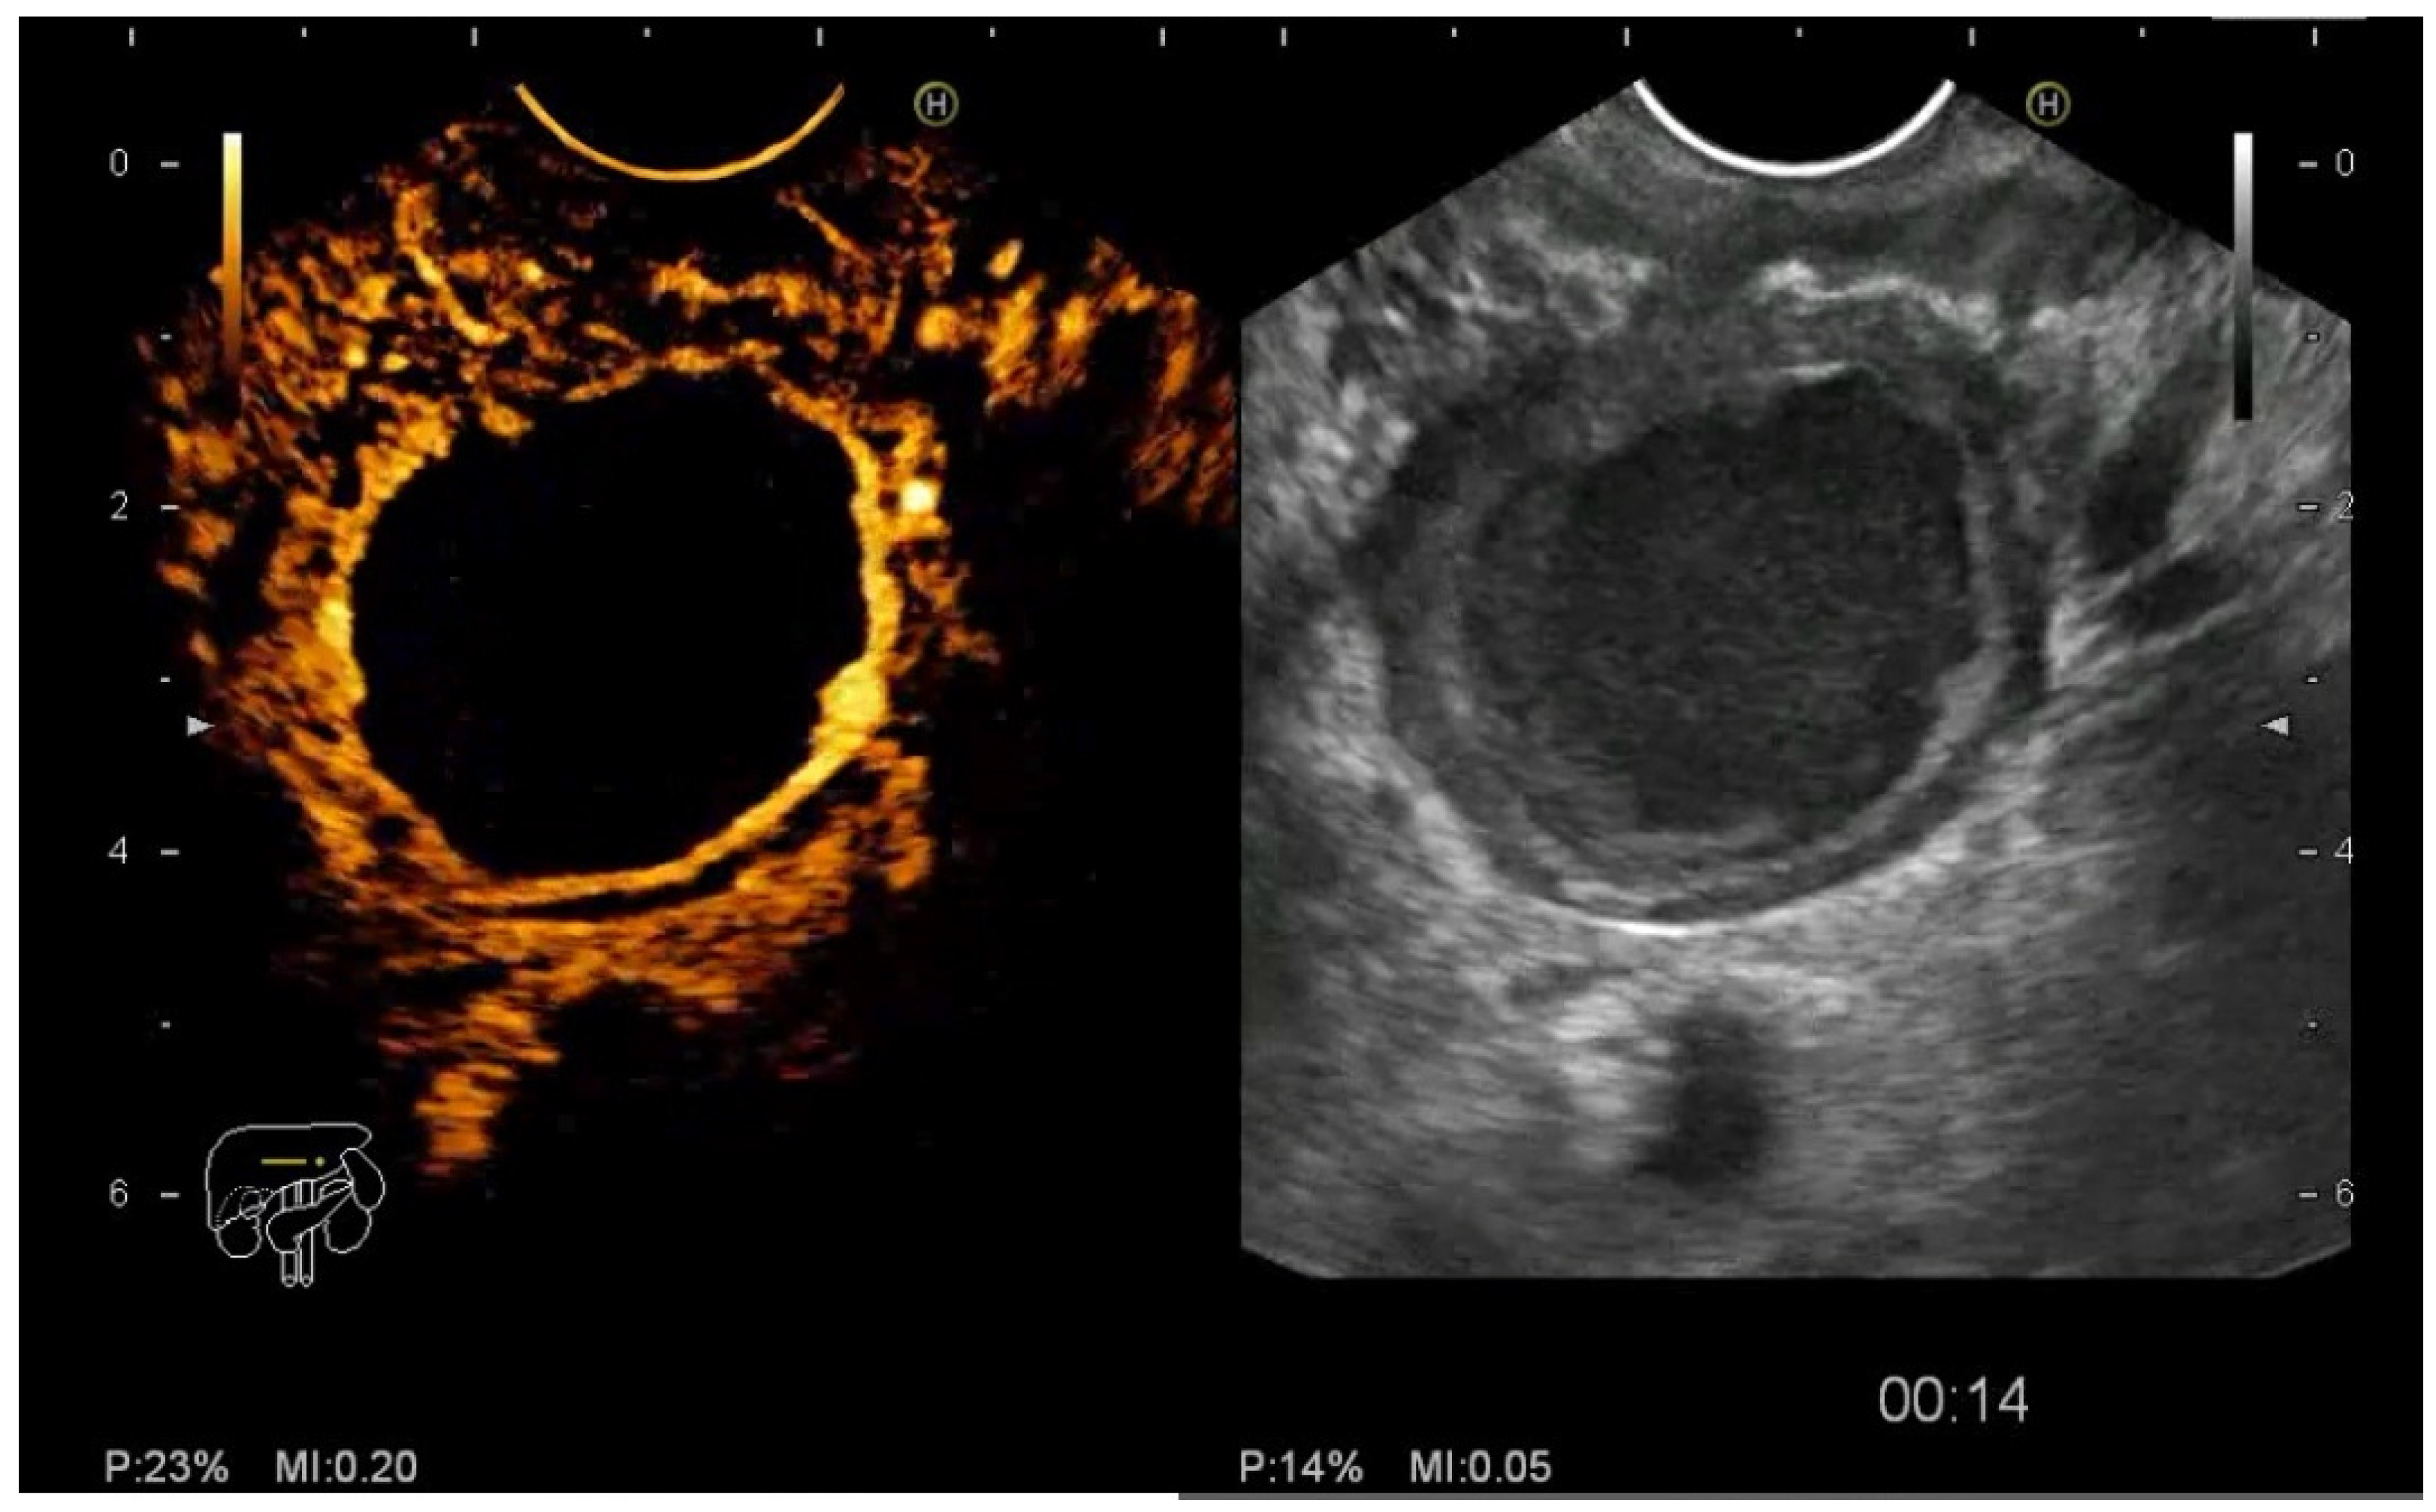

2.5. CE-EUS Procedure

- the entanglement of CE-EUS in describing pseudocysts and the benign/premalignant/malignant character of pancreatic cystic lesions

3.3. EUS-FNA/FNB + CE-EUS of Pancreatic Cystic Lesions Subgroup